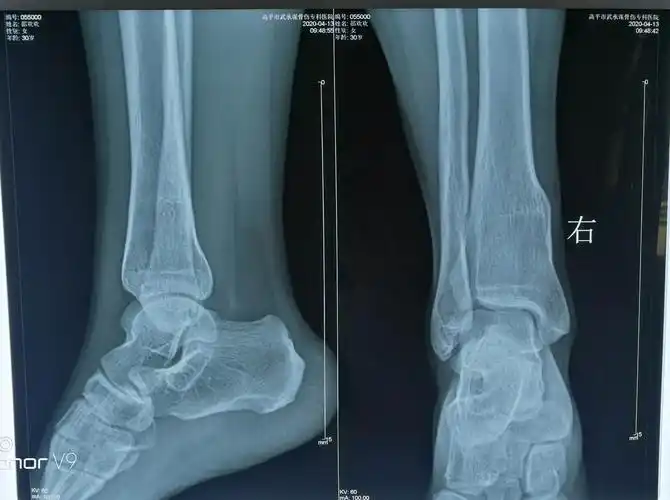

看看这个胫腓骨远端开放性粉碎性骨折治疗